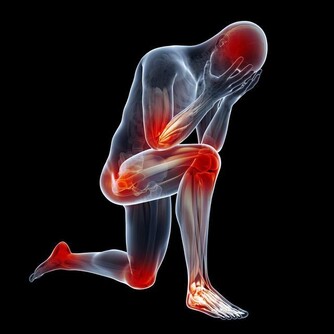

4、易生病,抵抗力下降: 我們生活的環境中,無處不存在著看不見的細菌病毒,因為身體擁有強大的免疫力才使我們免受這些病菌的感染。但長期生活在甲醛超標的環境會使免疫系統遭受破壞,降低人體抵抗力,不能有效地防禦外界病原微生物的侵入,從而導致疾病發生。家人入住新居後經常感冒,尤其是老人兒童,感冒後一個星期也不見好轉,這都可能是甲醛超標引起的。